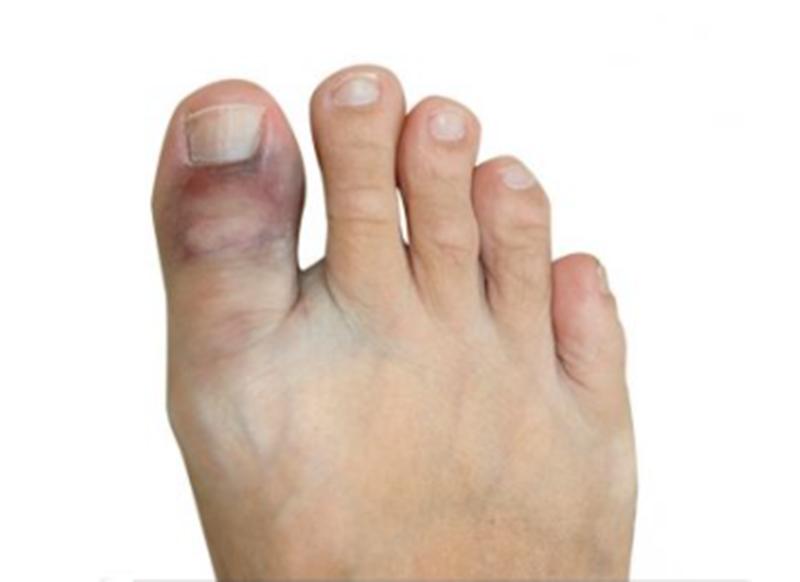

脚趾扭伤是指韧带过度拉伸或者撕裂,从而引起疼痛。但不会直接影响脚趾骨。 扭伤的症状包括疼痛、脚趾移动困难、肿胀、淤青和压痛。虽然每个人都可能扭伤脚趾,但 这些人风险最高:脚趾受过伤的,脚趾有痛风或者关节炎的,鞋子太宽或者太窄的, 根据严重程度扭伤分为三个等级。

- 1级:轻度扭伤,受伤的区域有一些压痛和肿胀,还能走路。

- 2级:中度扭伤,肿胀更严重,有淤青,脚趾运动范围变小,勉强可以走路。

- 3级:严重扭伤,韧带完全撕裂。疼痛剧烈,有严重肿胀和瘀伤。几乎不能移动脚趾和走路。

中到重度的扭伤可能和骨折难以分辨,都会出现肿胀、淤青,脚趾难以移动,站立和行走困难。尤其 撕脱性骨折 和应力性骨折,没有明显的外伤,容易和扭伤混淆。 撕脱性骨折是指一小块骨片被肌肉或者韧带从骨头上撕下来, 会出现肿胀、瘀伤以及脚趾关节活动困难。有时可能被误诊为扭伤,甚至采取了错误的治疗。